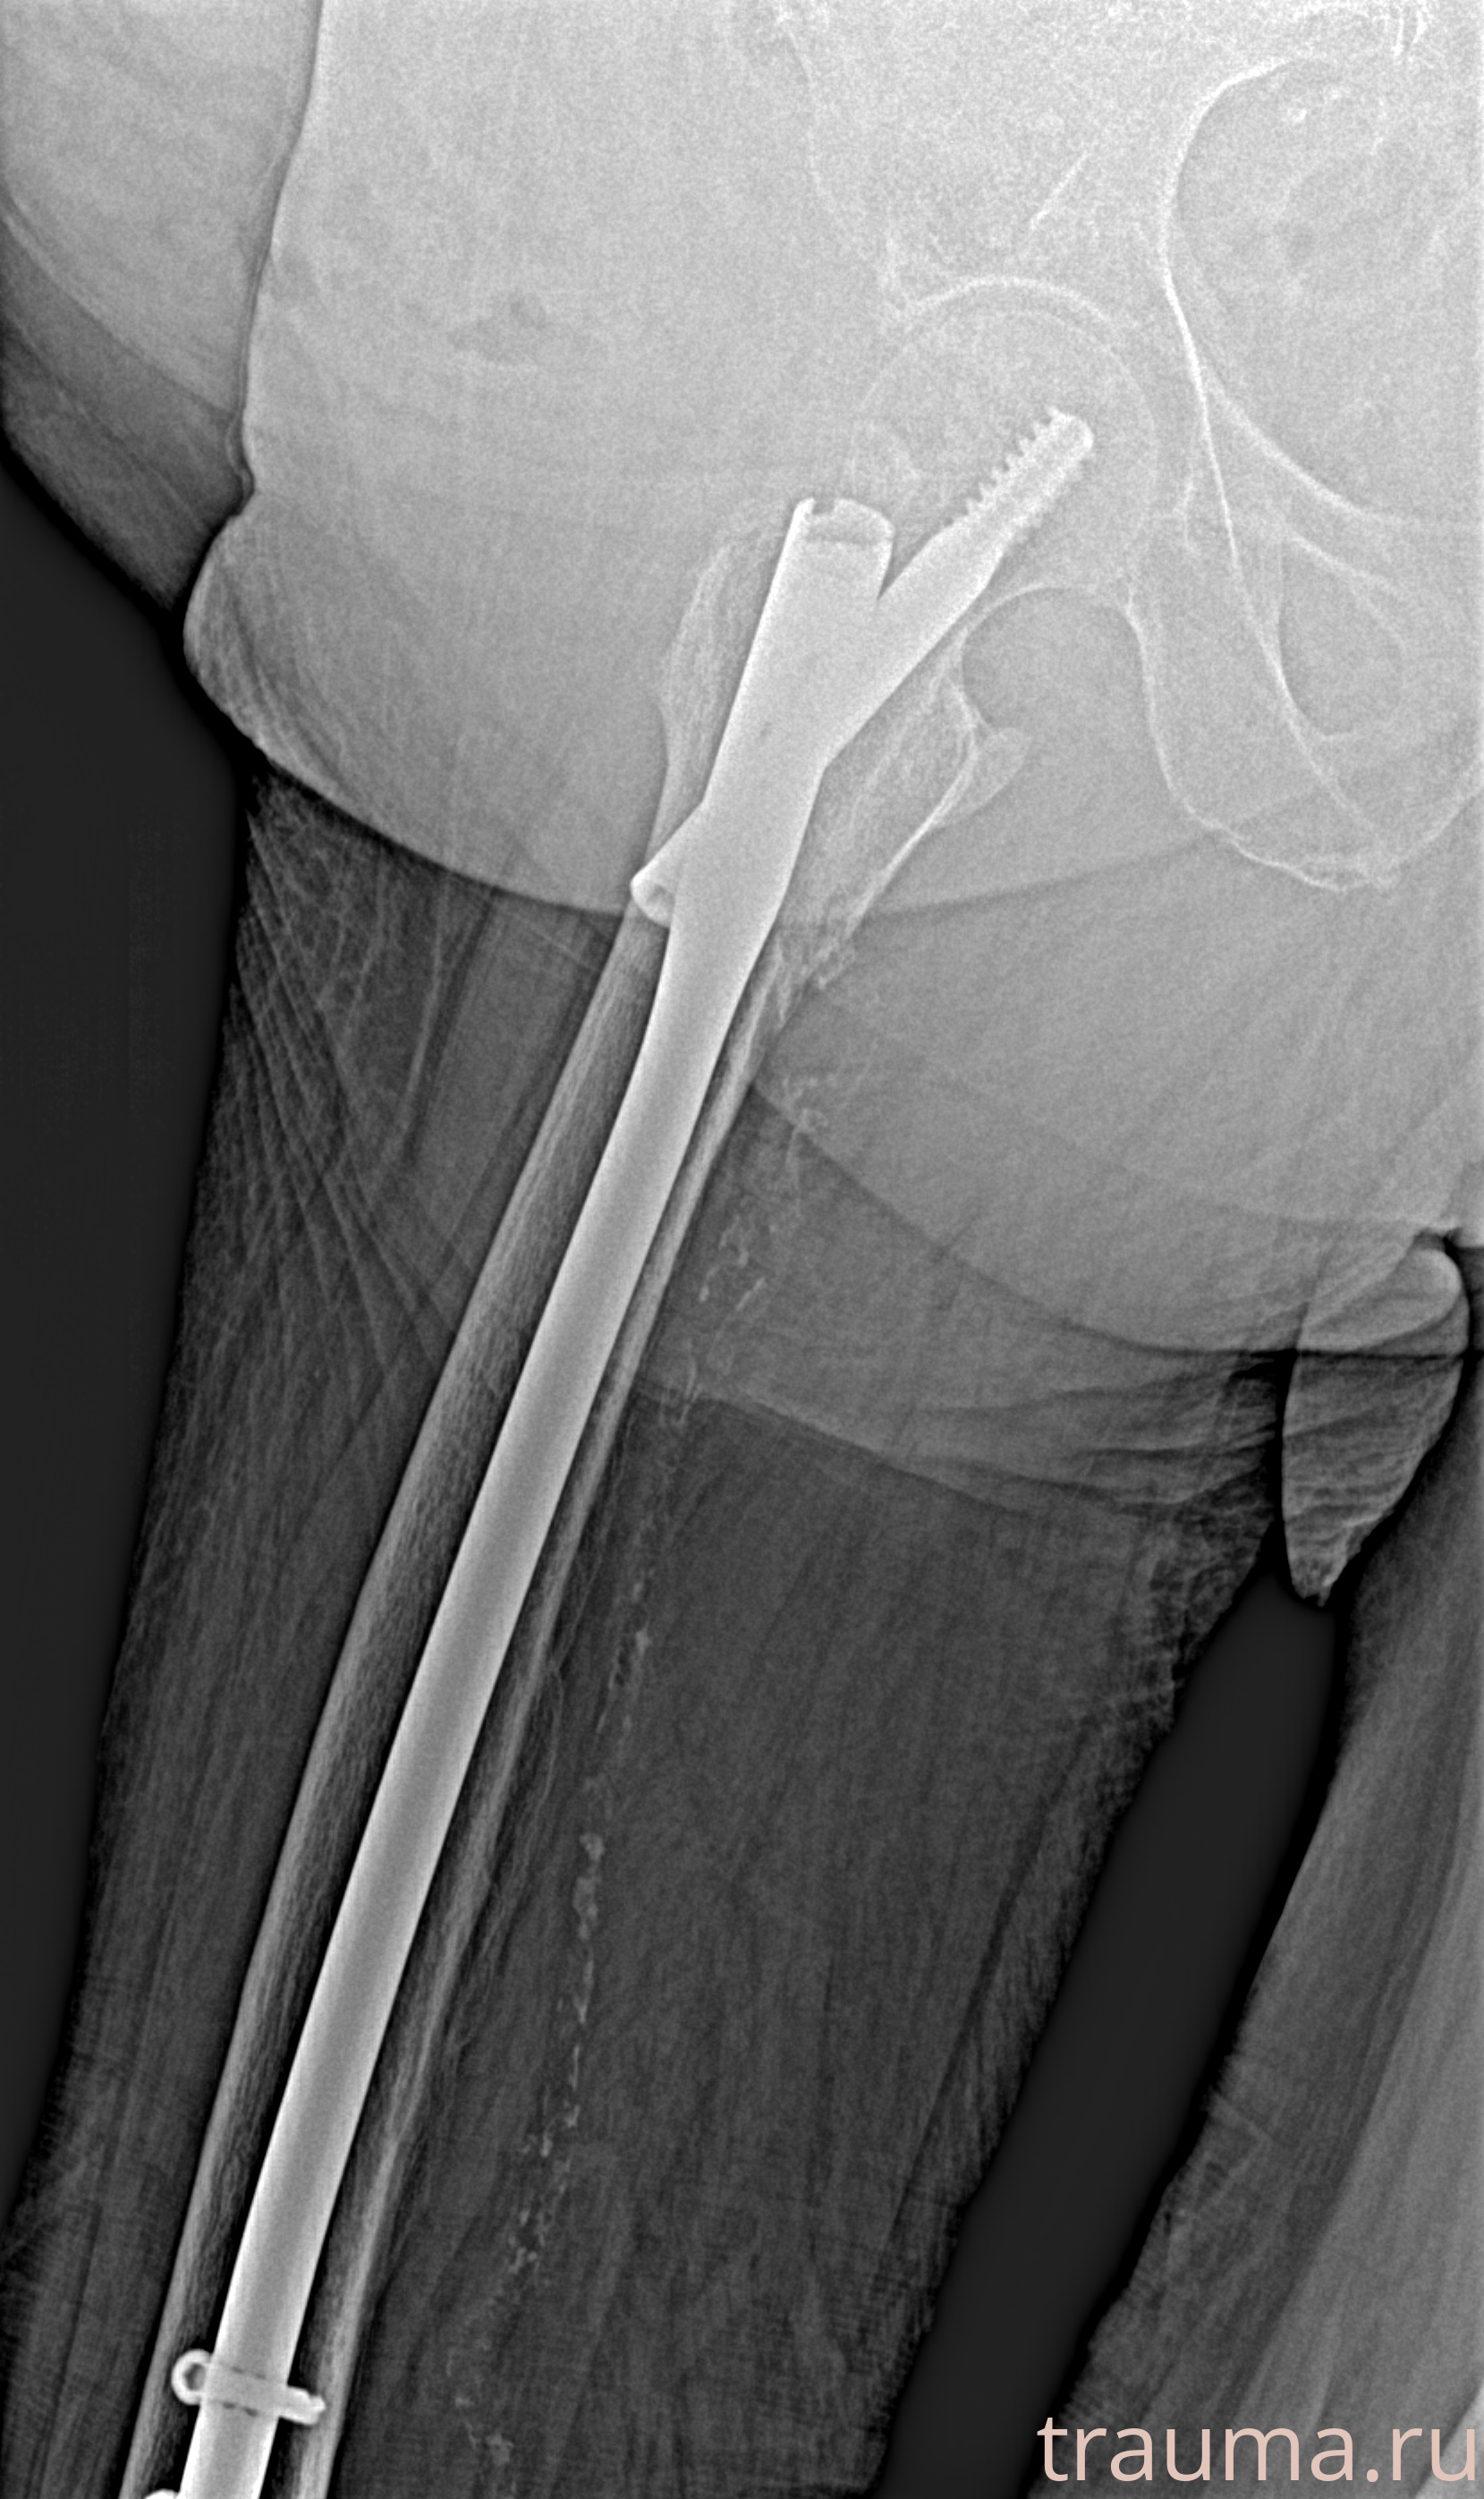

Рентгенограммы

Рентген на дому: по вашему адресу приезжает врач-рентгенолог, травматолог-ортопед с мобильным рентгеновским аппаратом, проводит диагностику травмы или заболевания, делает необходимые рентгенограммы, дает рекомендации по дальнейшему лечению. Получить качественные снимки в домашних условиях возможно благодаря уникальной методике, разработанной МосРентген Центром для института  Склифосовского